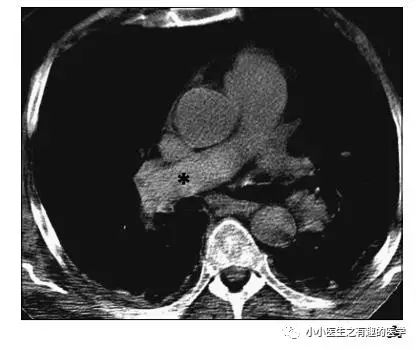

如图,高密度影的那一条。

不怕,有增强CT证实。